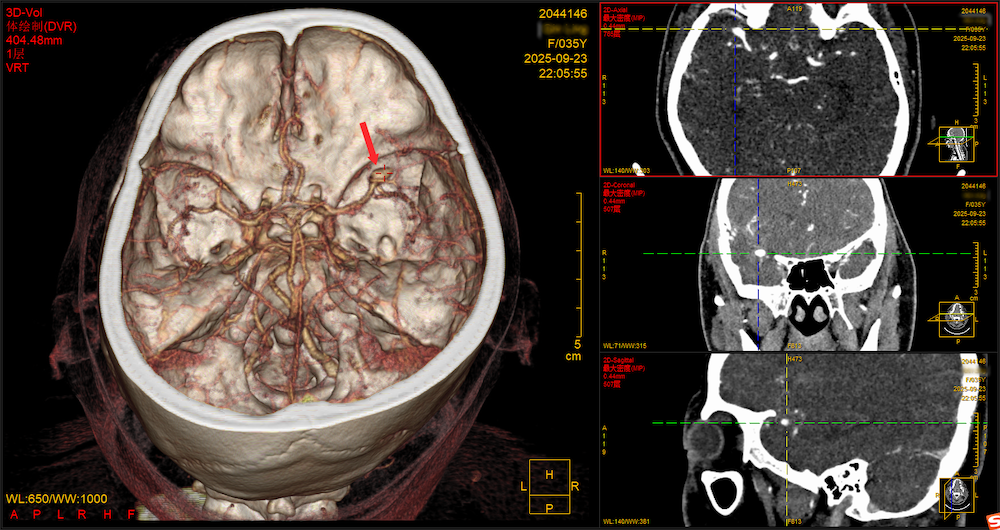

接诊医护立刻启动急救流程,CT影像很快给出答案:右侧大脑中动脉巨大动脉瘤破裂,颅内已出现广泛蛛网膜下腔出血——这是神经外科最凶险的急症之一,如同颅内藏了颗“定时炸弹”,随时可能二次破裂,死亡率极高。

9月24日0时30分,覃女士被推进手术室。此时窗外狂风呼啸,雨点砸在玻璃上噼啪作响;手术室内,无影灯照亮的是另一片“战场”:宝安区神经外科首席专家张力主任主刀,刘裕浩副主任医师密切配合,为患者进行紧急开颅脑动脉瘤夹闭手术。